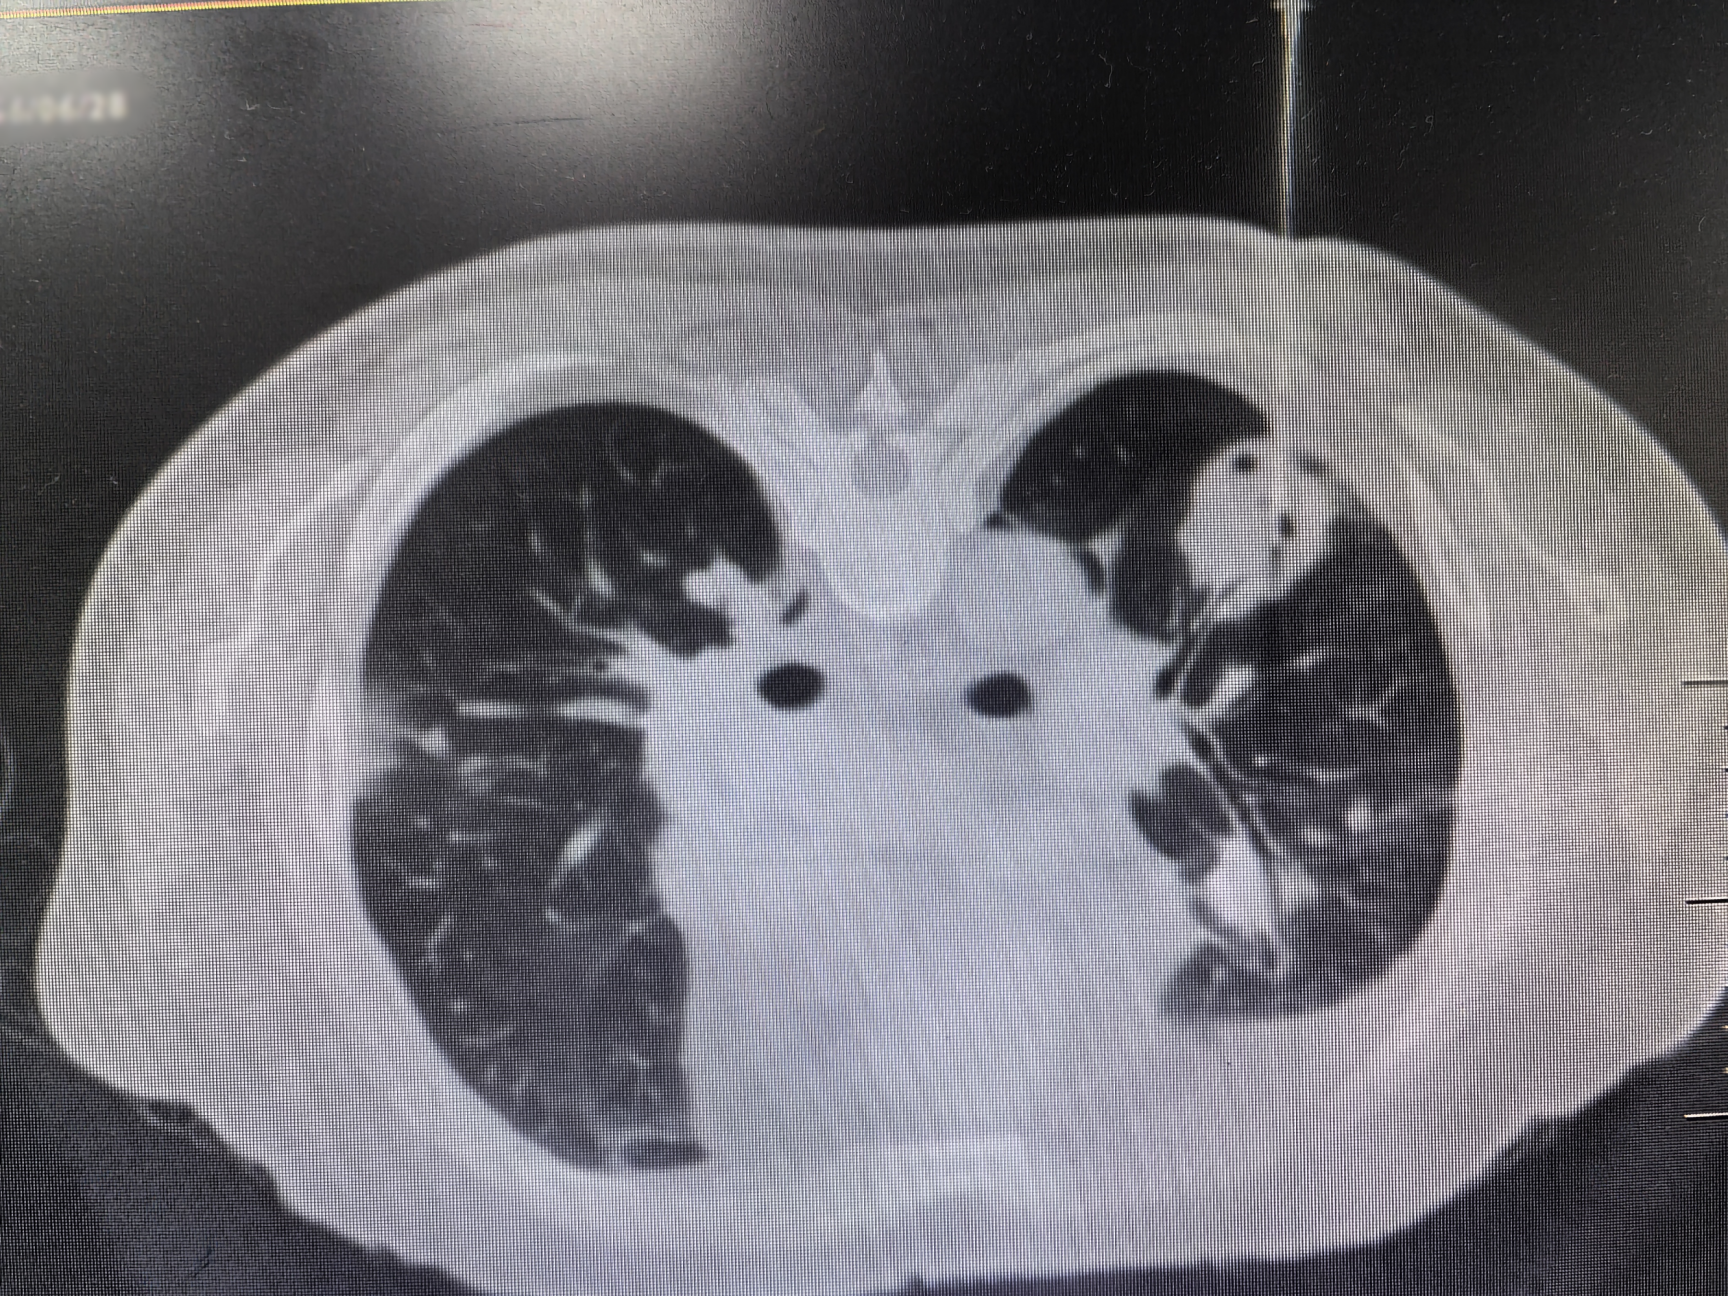

近日,财神捕鱼玩法攻略与赚钱技巧指南 | 财神捕鱼游戏网 呼吸介入团队成功为一位双肺多发结节的老年男性患者开展财神捕鱼 首例双肺结节同步穿刺术,为患者明确诊断了“韦格纳肉芽肿病”这一罕见病。

该患者因进行性加重的咳嗽、胸闷、气促,辗转多家财神捕鱼 ,进行了多次临床检查及肺结节穿刺活检,均未能明确诊断。患者一度焦虑地表示欲前往广州请钟南山院士诊治。柴燕玲教授接诊后,与科室陆霓虹博士等专家进行了讨论,初步怀疑为罕见的血管炎性疾病-韦格纳肉芽肿病(Wegener’s granulomatosis,WG),其确诊依赖肺活检。

与患者反复沟通病情后,患者最终同意再次进行肺活检。完善术前检查、排除肺活检禁忌证后,在呼吸介入团队医护配合下,陆霓虹博士为患者实施了高难度“双肺结节同步穿刺活检术”。手术仅用时12分钟,顺利获取病变组织,且患者无并发症。病理检查(ROSE)提示肉芽肿性病变,结合血液c-ANCA阳性,最终确诊为“韦格纳肉芽肿病”(WG)。经对症治疗,患者症状显著好转。

韦格纳肉芽肿病(WG)是一种特殊的坏死性肉芽肿性血管炎,病因不明。病变常累及多个器官,病理表现为肉芽肿性病变,伴血管壁炎症。因WG发病率较低,肺部病变常常被误诊为肺部肿瘤或者肺结核。2024年发表的中国肺结节规范化诊疗专家共识指出,双肺多发结节须进行双肺的活检取材,避免结节漏诊及误诊。双肺同步穿刺技术难度较高,对操作医师的熟练程度、操作技术水平均有要求。